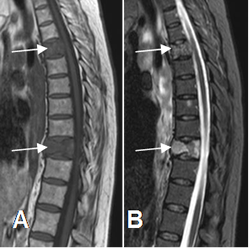

Fig 7. Señal anormal en STIR.

A: RM sagital en T1. Lesiones hipointensas en vértebras dorsales.

B: RM sagital en STIR. Aumento en la SI de las vértebras, por enfermedad metastásica de pulmón.